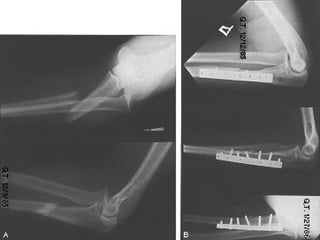

RELACION DE LOS FRAGMENTOS ENTRE SI Sin desplazamiento Con desplazamiento: lateral, angulada, rotación, diastasado, cabalgado, impactada

RELACION DE LOSFRAGMENTOS ENTRE SI Sin desplazamiento Con desplazamiento: lateral, angulada, rotación, diastasado, cabalgado, impactada